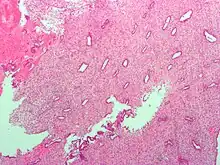

The endometrium consists of a single layer of columnar epithelium plus the stroma on which it rests. The stroma is a layer of connective tissue that varies in thickness according to hormonal influences. In the uterus, simple tubular glands reach from the endometrial surface through to the base of the stroma, which also carries a rich blood supply provided by the spiral arteries. In women of reproductive age, two layers of endometrium can be distinguished. These two layers occur only in the endometrium lining the cavity of the uterus, and not in the lining of the fallopian tubes.[4][5]

- The functional layer is adjacent to the uterine cavity. This layer is built up after the end of menstruation during the first part of the previous menstrual cycle. Proliferation is induced by estrogen (follicular phase of menstrual cycle), and later changes in this layer are engendered by progesterone from the corpus luteum (luteal phase). It is adapted to provide an optimum environment for the implantation and growth of the embryo. This layer is completely shed during menstruation.

- The basal layer, adjacent to the myometrium and below the functional layer, is not shed at any time during the menstrual cycle. It contains stem cells that regenerate the functional layer,[1] which develops on top of it.

It is possible to identify the phase of the menstrual cycle by reference to either the ovarian cycle or the uterine cycle by observing microscopic differences at each phase—for example in the ovarian cycle:

| Phase | Days | Thickness | Epithelium |

|---|---|---|---|

| Menstrual phase | 1–5 | Thin | Absent |

| Follicular phase | 5–14 | Intermediate | Columnar |

| Luteal phase | 15–27 | Thick | Columnar. Also visible are arcuate vessels of uterus |

| Ischemic phase | 27–28 | Columnar. Also visible are arcuate vessels of uterus |